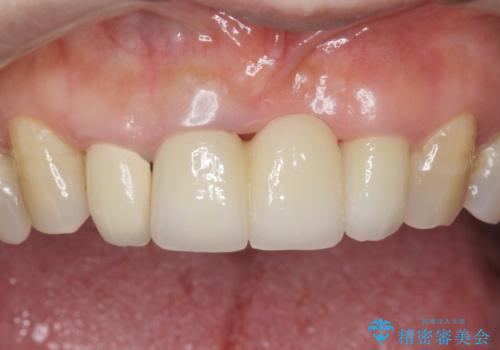

自然な仕上がりと使い心地に喜んで頂けました。

奥歯の治療もやりたいとおっしゃって下さり、今後進めていく予定です。

~被せ物の種類~

ジルコニアクラウン スタンダード

- ¥1,010,000 (仮歯×9本、ファイバーコア×1本、ジルコニアクラウン スタンダード×9本)費用は治療当時の料金となります